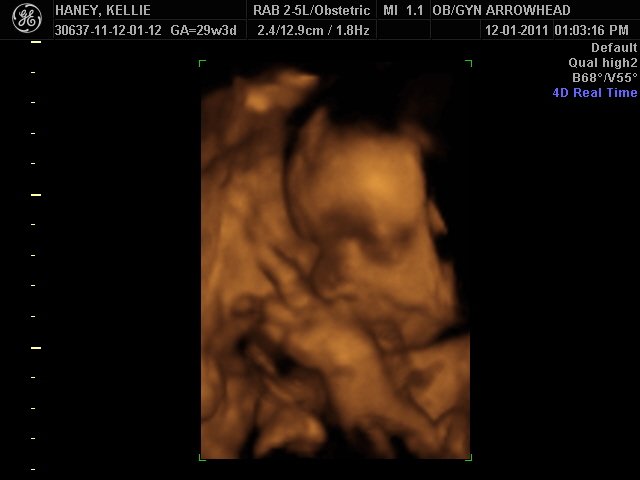

We offer complimentary 3D/4D Ultrasounds to all our OB patients around 30 weeks! The following photos are some examples of our work, shown with permission from our patients.